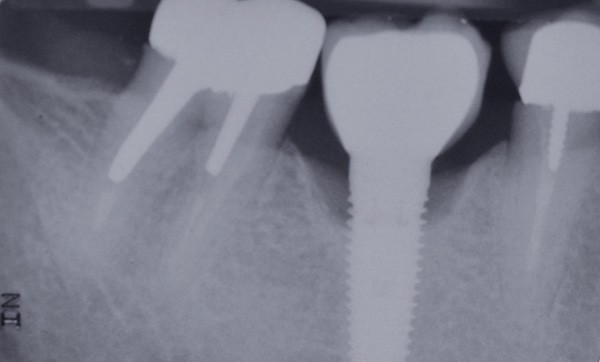

La stabilité des tissus mous autour des implants apparaît également comme un facteur très déterminant. L’absence de barrière kératinisée stable crée une mobilisation haute des tissus jusqu’au col implantaire. Cela a pour conséquence l’apparition de déhiscence gingivale, puis la disparition de l’os vestibulaire ou lingual.

La surface implantaire, ainsi exposée, fait office de porte d’entrée bactérienne. L’état de surface et sa capacité à fixer plus ou moins facilement les bactéries jouent alors un rôle primordial dans l’évolution de la pathologie.

Ce sujet est depuis de nombreuses années discuté et étudié dans le monde de l’implantologie. Il est évident que certaines surfaces présentent, soit par leur mode d’obtention, soit par leur niveau de rugosité, davantage de risques.